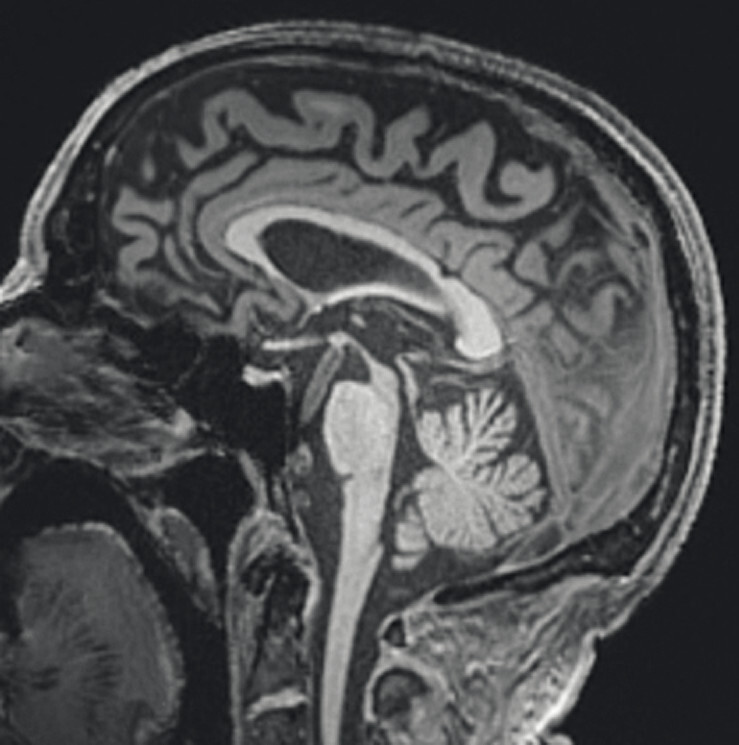

Abb. 69.10 Parkinson-Syndrome: Differenzialdiagnose progressive supranukleäre Parese mit Parkinson-Syndrom.

74-jähriger Patient mit linksbetontem Parkinson-Syndrom und aktuell deutlicher demenzieller Entwicklung mit exekutiver Störung und Zeitgitterstörung. In der T1w 3-D-MRT zeigt sich ein unauffälliges Mesenzephalon (a) mit einer normalen Midbrain/Pons-Ratio von 0,61 (kurzer Durchmesser des Mesenzephalons: 9,9 mm; kurzer Durchmesser des Pons: 16,1 mm, beide durch eine rote Linie dargestellt; b). Die automatisierte Ganzhirnvolumetrie (c) lässt außerdem ein anomales Hirnvolumen frontal bis parietal beidseits erkennen. In der 2 mm dünnen transversalen SWI-Schicht findet sich kein Schwalbenschwanzzeichen (d).

a T1w 3-D-MRT-Sequenz.

b T1w 3-D-MRT-Sequenz mit eingezeichneten Durchmessern.

c Ganzhirnvolumetrie.

d Transversale SWI.